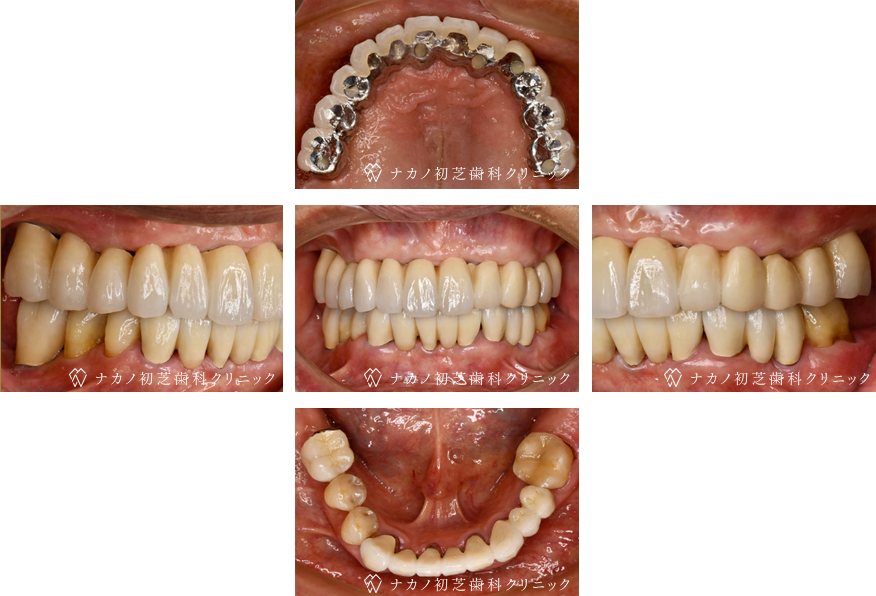

インプラント・7本 (60代男性)

BEFORE

AFTER

年齢 60代男性

治療内容 インプラント治療7本(骨造成の併用)

インプラント治療とは、歯を抜いた所にチタン製の人工歯根を埋入し、その上に歯を入れる方法です。骨を増やすことで、より審美的に治療が出来ました。費用 1本 400,000円(税込 440,000円)

リスク・副作用

腫れ・疼痛・違和感を感じるなどの症状を生じることがあります。